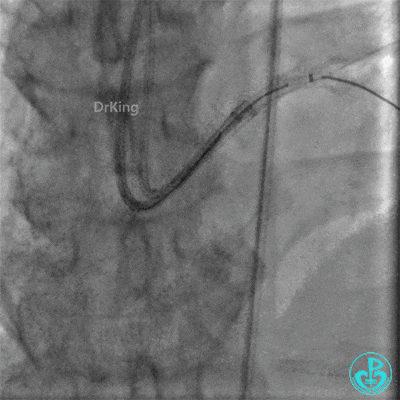

右桡动脉入路6F EBU 3.75指引导管到位,Corsair 150微导管辅助,Sion导丝尝试通过侧支。

Corsair微导管跟进困难,换Finecross 150微导管,通过侧支到达前降支闭塞远端血管真腔。